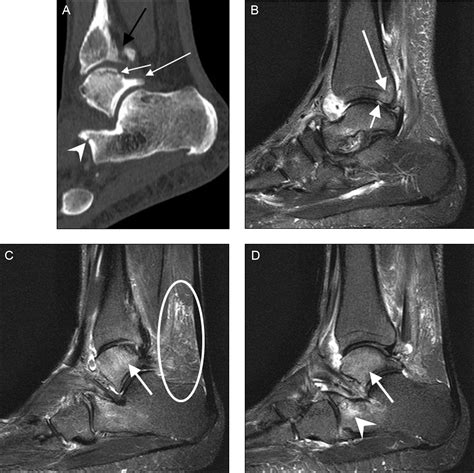

Imaging tests, such as X-rays, MRI, or CT scans, can provide detailed images of the ankle joint and surrounding structures. These tests can help identify any abnormalities, such as bone spurs, fractures, or soft tissue damage, that may be contributing to the symptoms.

• posterior ankle impingement mri